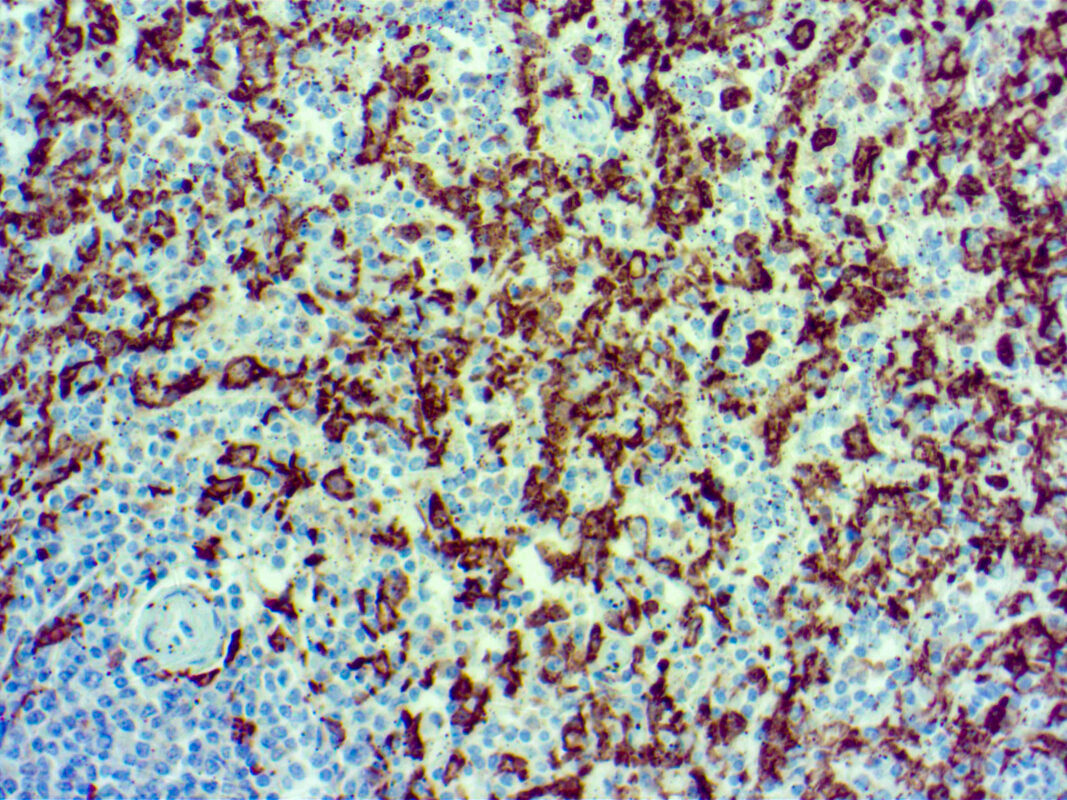

Iba1Spleenx2512022A min Published June 6, 2022 at 2560 × 1920 in Iba1Spleenx2512022A min Formalin fixed paraffin embedded human spleen tissue stained with Iba1 Iba1Spleenx2512022A min ← Previous Next →